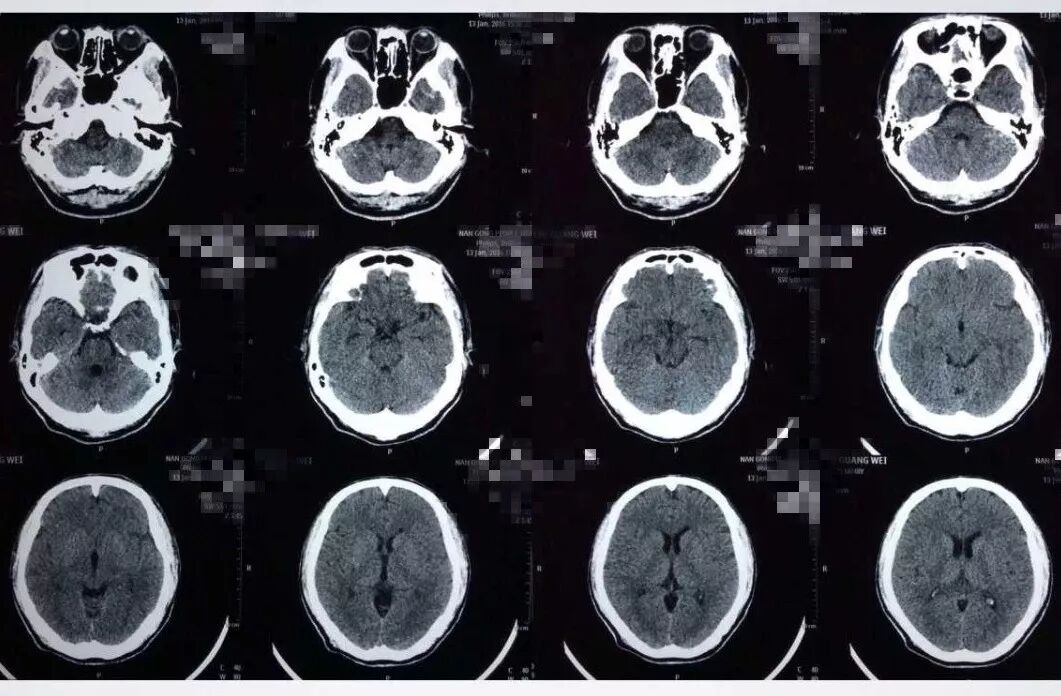

患者缘于10天前无明显诱因突发头痛伴呕吐,于当地医院就诊查头部CT提示:SAH;遂于当地医院予以保守治疗,其后症状逐渐好转;于发病9天后突然出现右眼眼睑下垂及右眼视物不清,遂到河北医科大学第二医院东院区就诊。头部CT提示未见明显出血;头部CTA提示:右侧后交通动脉动脉瘤及左侧脉络膜前动脉动脉瘤。

发病当天CT